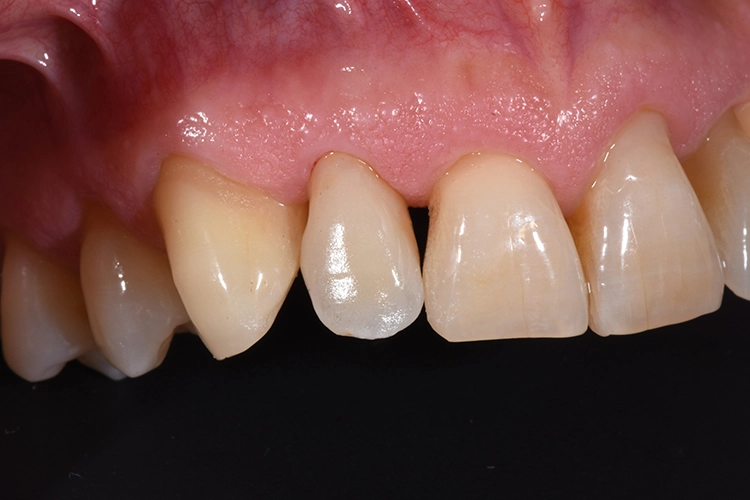

Hieraus ergibt sich, dass bei Jugendlichen und jungen Erwachsenen eine implantologische Behandlung im ästhetischen Bereich möglichst lange herausgeschoben oder vermieden werden sollte, die Suche nach Alternativen zum Zahnimplantat ist naheliegend [5]. Subgingivale Defekte gelten schnell als nicht restaurierbar und die Zähne somit als nicht erhaltungswürdig.

Zahlreiche Studien bestätigen den Gedanken, dass ein ausreichendes Ferrule Design für die Langzeitstabilität eines überkronten Zahnes von ausschlaggebender Bedeutung ist. Es sollten mindestens 2-3 mm des eigenen Zahnes durch die Präparation gefasst sein [6].

Um das bei tief koronal oder subgingival frakturierten Zähnen erreichen zu können, bieten sich dem Behandler verschiedene Möglichkeiten. Zum einen kann durch eine chirurgische Kronenverlängerung Zahnhartsubstanz freigelegt werden, wobei man hier in aller Regel mit einem deutlichen Verlust der Ästhetik rechnen muss, vor allem wenn es sich um eine unilaterale Therapie handelt [7]. Eine Alternative ist die Extrusion des Zahnes aus der Alveole, hierbei werden in der Literatur sowohl die kieferorthopädische Extrusion als auch die intraalveoläre Transplantation beschrieben [8].